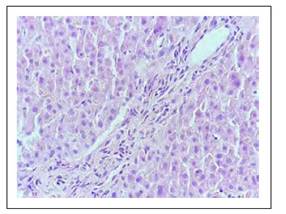

Los hallazgos histológicos en la biopsia hepática se muestran en las Figuras 1 a 6.

Figura 5 Espacio porta mediano, sin conducto biliar principal, hallazgo presente en más del 50% de los porta, es decir hay ductopenia.